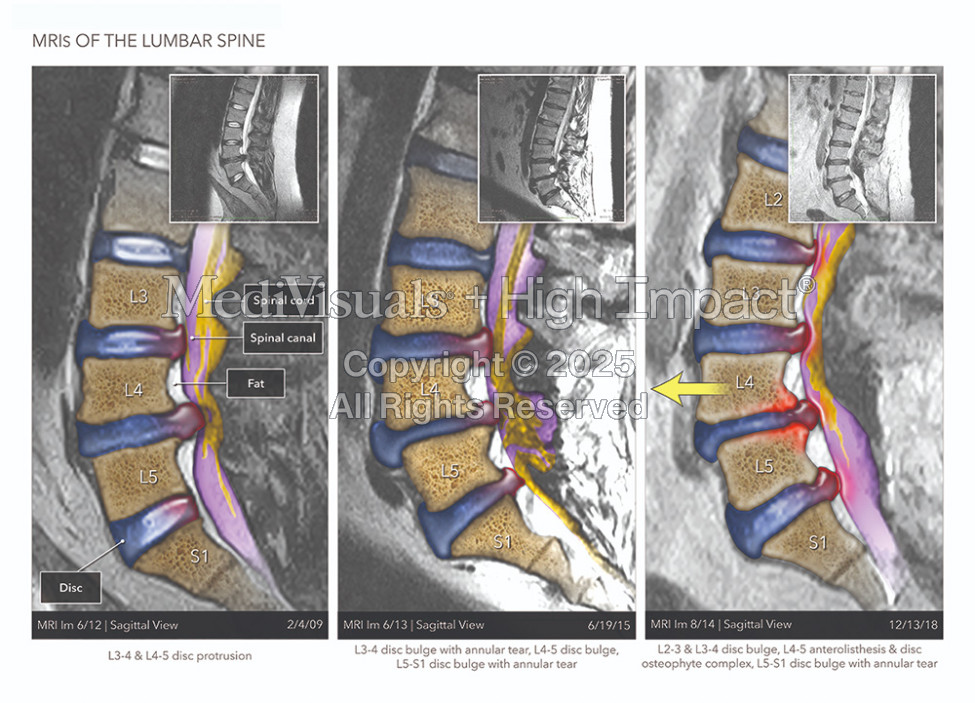

$1.55M Settlement: Colorized MRIs and Medical Illustrations Effectively Show New Injuries Suffered by Motorcyclist

When a motorcyclist suffered injuries from a crash, Judd R. Allen needed to definitively show that the injuries his client experienced were new and significant, even though he had been in a different motorcycle crash 3 years before this incident. The colorized MRIs and medical illustrations were so compelling that the case successfully settled for $1.55M.